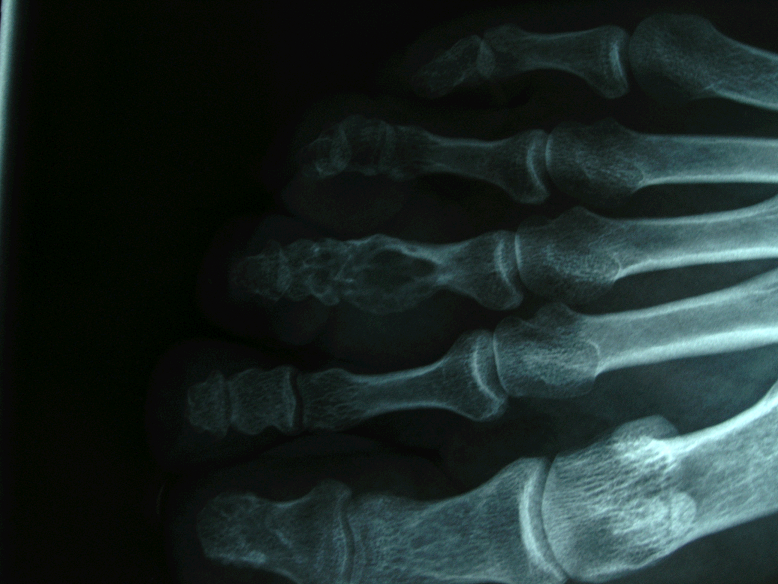

患者,男,30岁,右足第三趾近节腱鞘巨细胞瘤并骨破坏,行肿瘤切刮除及异体骨植骨术。

术前X线片